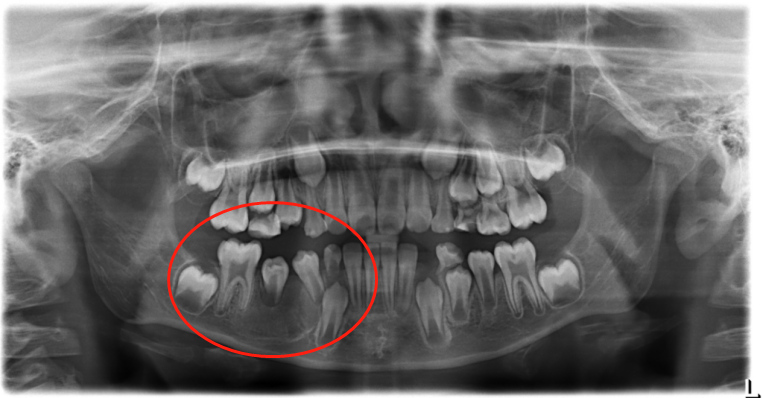

在术后第十天,鹏鹏到院复查,囊腔成愈合状态,恢复良好,继续佩戴阻塞器,保持开窗减压;术后四个月,鹏鹏进行X光片复查,显示囊肿界限开始模糊,囊腔面积缩小,囊肿包裹的恒牙有萌出迹象;术后十个月,囊肿已经消失,囊腔愈合,恒牙萌出。但是王静静医生表示,由于鹏鹏的恒牙没有全部萌出,牙齿的后续发育情况会怎样,无法预知,需持续追踪,同时希望家长定期带鹏鹏进行检查,监测牙齿和颌面部的发育情况。

(术后四个月X光片)